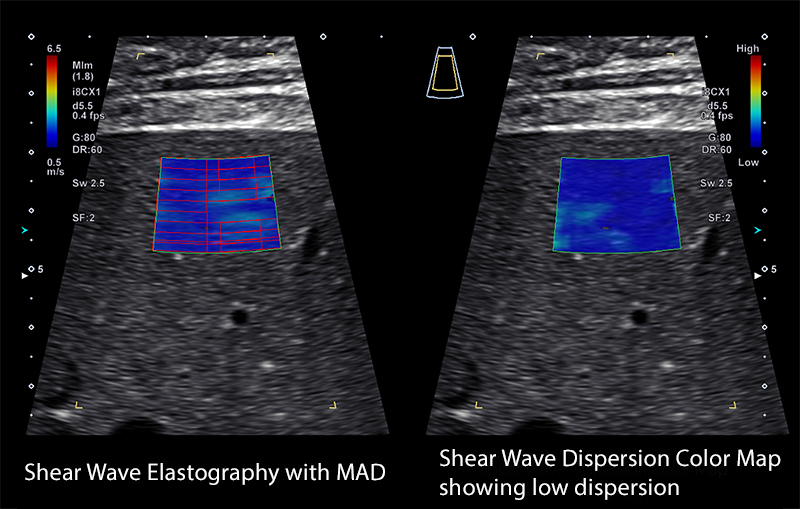

Shear Wave Dispersion (SWD) - A viszkozitás elemzése a szöveti merevség mellett

A szöveti merevség változásai gyakoriak a májbetegségekben, azonban a viszkozitás változásainak kimutatása – például a zsíros infiltráció vagy gyulladás miatt – korábban nem volt lehetséges.

A SWE és SWD kombinációja egyszerre nyújt információt a merevségről és a viszkozitásról, így a máj komplexebb értékelését teszi lehetővé.

Gyulladásos folyamatok esetén a májszövet viszkózusabbá válik, és ezeket a változásokat az SWD képes kvantifikálni.

Shear Wave Elastography (SWE)

Noninvazív, kvantitatív szöveti merevségmérés

A Canon Shear Wave technológiája kvantitatív és dinamikus vizuális információt nyújt a szöveti merevségről különböző klinikai környezetekben.